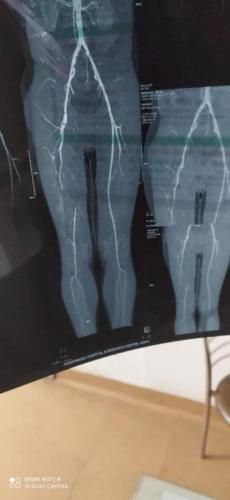

Photo Gallery Dr. Monika Gupta - Photo Gallery 7 5 2 8 6 Dr. Atul Kumar Gupta - Photo Gallery « ‹ of 3 › » Video Gallery